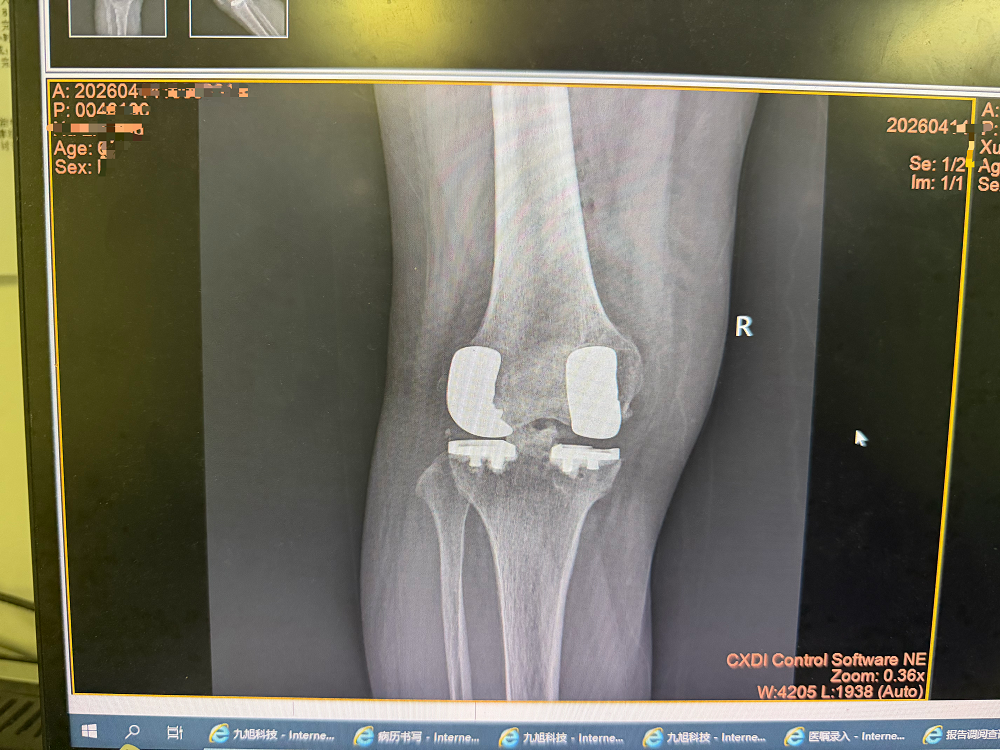

手术过程中,骨科团队凭借精湛的微创技术,精准定位、精细操作,严格把控下肢力线与假体安装角度,顺利完成双间室假体精准植入,假体匹配度优良,关节屈伸功能平衡,手术圆满成功。术后复查影像学显示,膝关节假体位置精准、力线恢复正常,患者术后即刻膝关节疼痛大幅缓解,次日即可下地进行康复锻炼,关节屈伸活动恢复理想,目前已顺利康复,患者及家属对治疗效果高度认可。